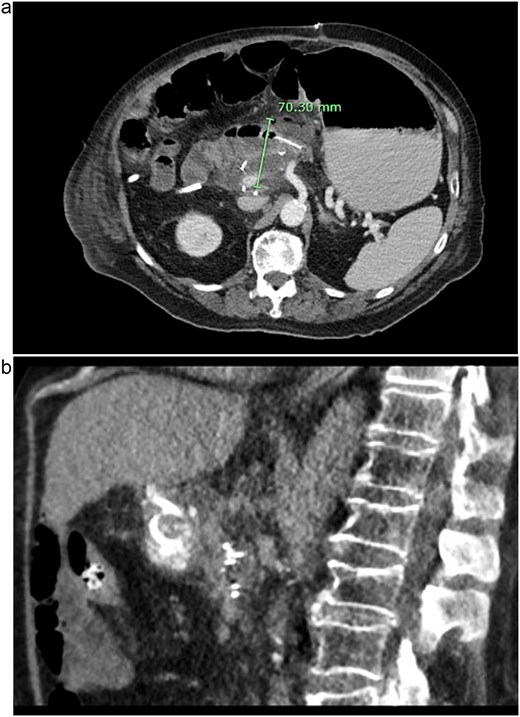

Post-operatively, NGT removal was delayed to post-op day (POD) 3 due to persistently high output. The patient required daily enemas, and his first bowel movement was on POD 7. He was gradually advanced to a low-fat regular diet, while JP drains remained serosanguinous with low drain amylase levels. Unfortunately, he developed a fever of 102.5°F on POD 9 and sudden onset abdominal pain. CT imaging showed a 6 cm fluid collection posterior to the PJ, a persistently dilated stomach, and a high colonic stool burden. An NGT was replaced and total parenteral nutrition initiated. The patient then underwent IR guided aspiration and drainage of the fluid collection within 24 h of symptom onset. After percutaneous drainage, the patient improved clinically. However, ~12 h after drain placement, the drainage changed from purulent to bilious in color. Repeat CT imaging demonstrated that the IR drain had ultimately been positioned within the lumen of the blind end of the afferent limb (see Fig. 3).

CT images of this patient’s post-operative pancreatic fistula (a) prior to IR guided intervention; (b) after percutaneous jejunostomy that was confirmed to rest within the blind jejunal end of the afferent loop after pancreaticoduodenectomy.